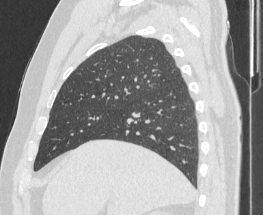

Мультиспиральная компьютерная томография органов грудной клетки представляет собой рентгеновское исследование костных структур грудной клетки, легочной ткани, бронхиального дерева, органов средостения.

Информативность МСКТ органов грудной клетки дополняет функциональная проба, то есть методика проведения сканирования на вдохе (инспираторная КТ) и на выдохе (экспираторная КТ). При выполнении КТ на вдохе с задержкой дыхания удается добиться максимального контраста между наполненными воздухом легкими и более плотными структурами, такими как плевра, стенки бронхов и кровеносные сосуды. Кроме того, на фоне пневматизированных легких хорошо видны очаговые и диффузные патологические изменения.

При экспираторной пробе (пробе на выдохе) можно выявить воздушные ловушки (то есть стойкое повышение пневматизации легочной ткани) на фоне пневмонитов, бронхиолитов, обструктивных заболеваний легких, эмфиземы.

Компьютерная томография в нашей клинике проводится на современных мультиспиральных томографах, которые производят тончайшие срезы исследуемой области и создают трехмерные изображения всех структур грудной клетки высокой четкости и контрастности. Увеличенное количество детекторов, которыми оснащены аппараты, обеспечивают быстрое сканирование зоны исследования при минимальных дозах рентгеновского облучения.